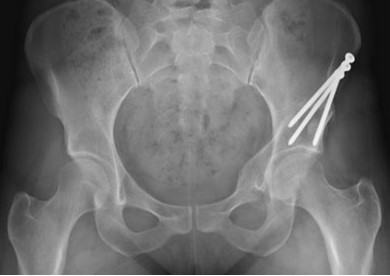

고관절 인공관절술 (치환술)

고관절 인공관절술 (치환술)은 외상 및 다양한 질환에 의해 고관절이 손상되어 보행이 어려운 환자에게, 손상된 관절을 재건하여 원활한 환자의 보행을 가능케 하는 수술입니다. 1950년경부터 시작된 현대 인공관절은, 정형외과 내에서도 그 역사가 가장 오래된 수술 중 하나로, 다른 어떤 정형외과 수술보다도 만족스러운 결과를 보고하고 있습니다.

손상된 관절 대신 인공관절을 삽입하여 통증을 완화해주고 경직된 운동범위를 확보하는 고관절 인공관절은 주로 관절염, 대퇴골두 무혈성 괴사, 고관절 골절 등에서 시행될 수 있습니다.